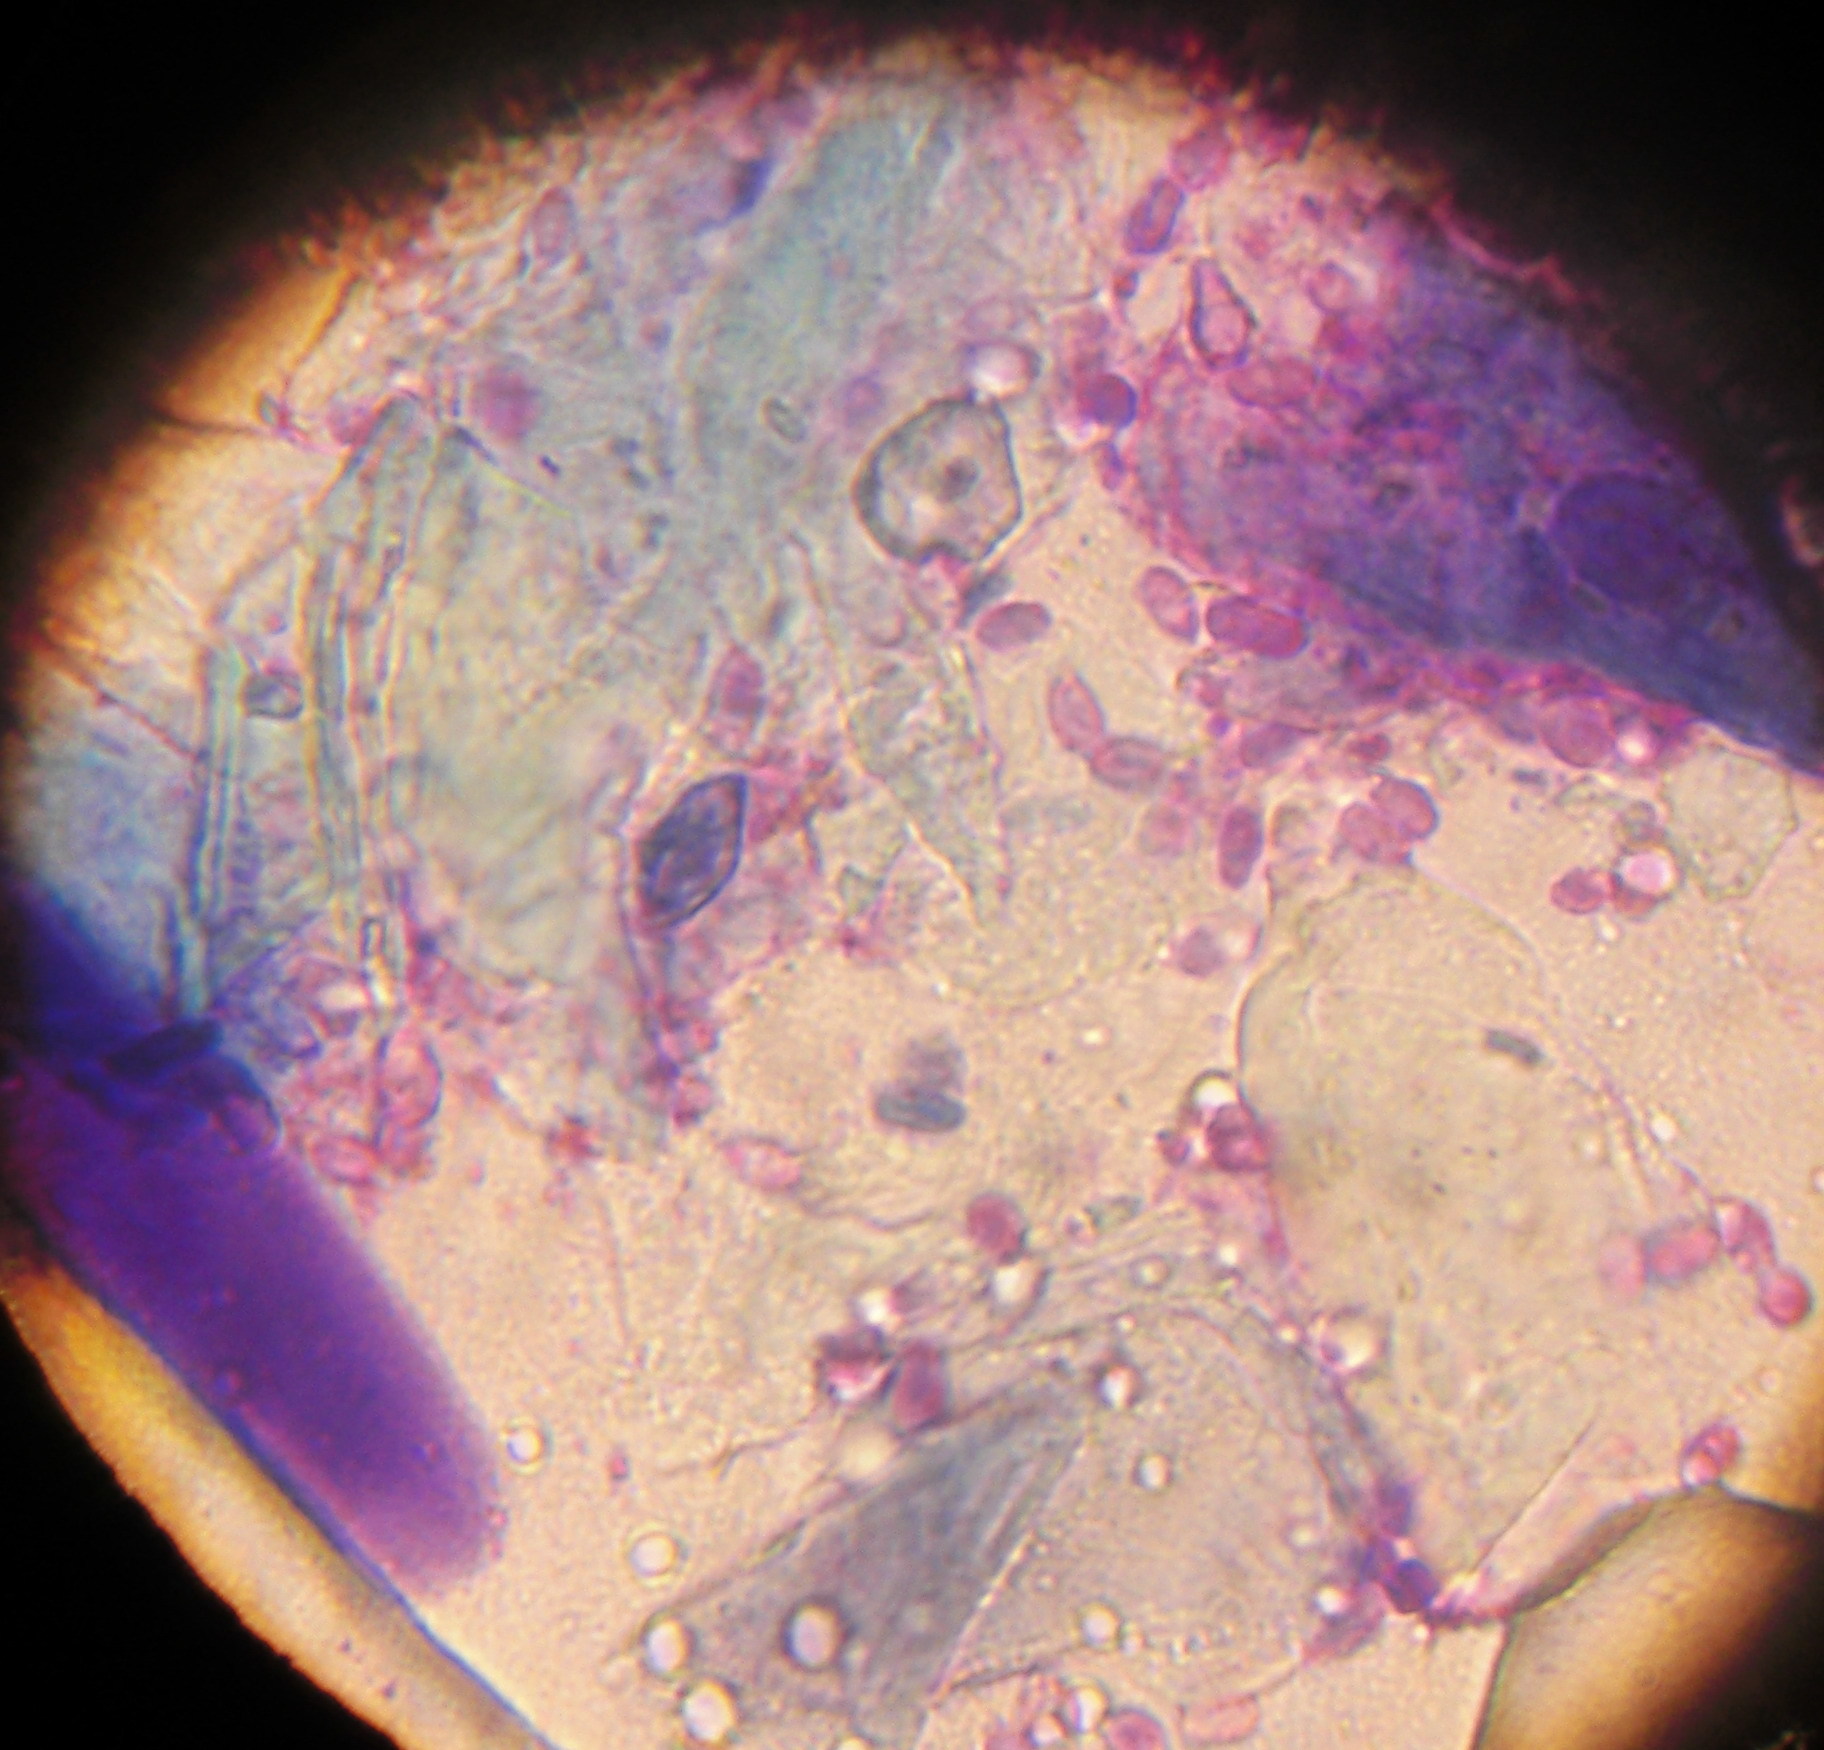

Um die Ursache für Lisas juckende Hautveränderung herauszufinden, werden nun Hautgeschabsel und Abklatschpräparate von der veränderten Haut genommen. Beim Hautgeschabsel werden mit einer mit Öl befeuchteten Skalpellklinge entweder oberflächlich oder aus tieferen Hautschichten Zellen und Material gewonnen. Auf diese Weise können verschiedene Milben nachgewiesen werden. Bei Lisa können jedoch keine Milben gefunden werden. In den Abklatsch-Präparaten - hier wird ein Tesastreifen oder ein Objektträger direkt auf die veränderte Hautstelle gedrückt und anschließend gefärbt - zeigen sich viele Hefepilze und Bakterien.